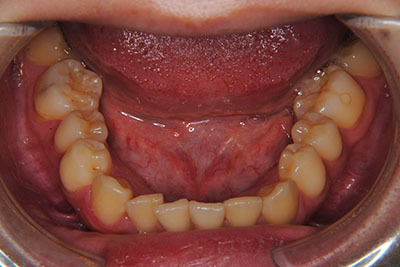

お口の中を診ますと、左上第二小臼歯が歯列の内側に生え、左上犬歯のスペースは全くない八重歯となっていました。検査結果から骨格的な不正はなく。上奥歯が前にずれたかみ合わせで前歯は合っていて出っ歯ではないので左右1本ずつ歯列からはみ出した状態であることがわかりました。上の奥歯を横の歯1本分後ろにずらすことは困難なので、右上中側に生えている第二小臼歯と八重歯である左上犬歯の次の歯=第一小臼歯の2本を抜歯し治療しました。